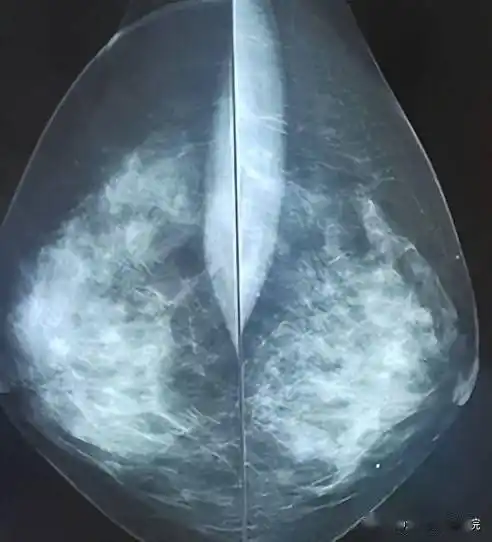

协和牵头制定中国指南发表b超是最适合国人的乳腺癌筛查手段